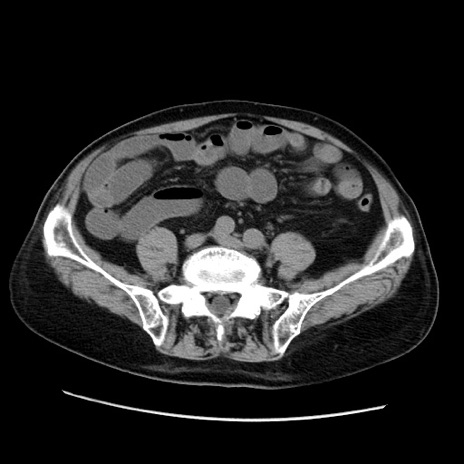

冠状断像

【症例】70歳代男性

【主訴】腹痛

【現病歴】肝硬変・肝細胞癌にてかかりつけの方。約9時間前に食後より腹痛出現。症状が徐々に増悪し、嘔吐出現したため来院。

【既往歴】肝硬変、肝細胞癌(RFA、TACE後)

【身体所見】意識清明、表情苦悶様、BT 36℃、BP 129/78mmHg、P 88bpm、SpO2 97%(RA)、右上腹部から心窩部にかけて圧痛あり、反跳痛なし、筋性防御あり。

【データ】WBC 5800、CRP 0.16